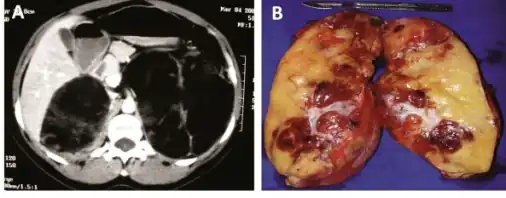

a)CT scan showing heterogeneous bilateral myelolipomas b) macroscopic aspect of left adrenal myelolipomas

Myelolipomas are usually found to occur alone in one adrenal gland, but not both. They can vary widely in size, from as small as a few millimetres to as large as 34 centimeters in diameter. The cut surface has colours varying from yellow to red to mahogany brown, depending on the distribution of fat, blood, and blood-forming cells. The cut surface of larger myelolipomas may contain haemorrhage or infarction.[1]

The cut surface shows colour variegation from yellow to red to brown depending on the distribution of fat, blood and myeloid elements -